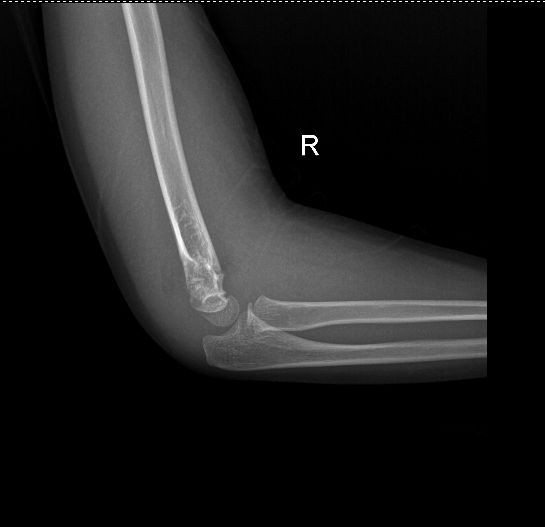

专科检查:步入病房,查体合作。右肘关节肿胀,局部压痛阳性,纵向叩击痛阳性,肘关节功能活动受限明显。肘后三角失常,可触及骨擦音及骨擦感,右上肢皮肤感觉正常,末梢血液循环好。远端手指未见肿胀,各手指感觉、运动良好。 右肘关节正侧位片 :右侧肱骨远端骨质断裂,断端旋转移位。周围软组织肿胀,层次不清。